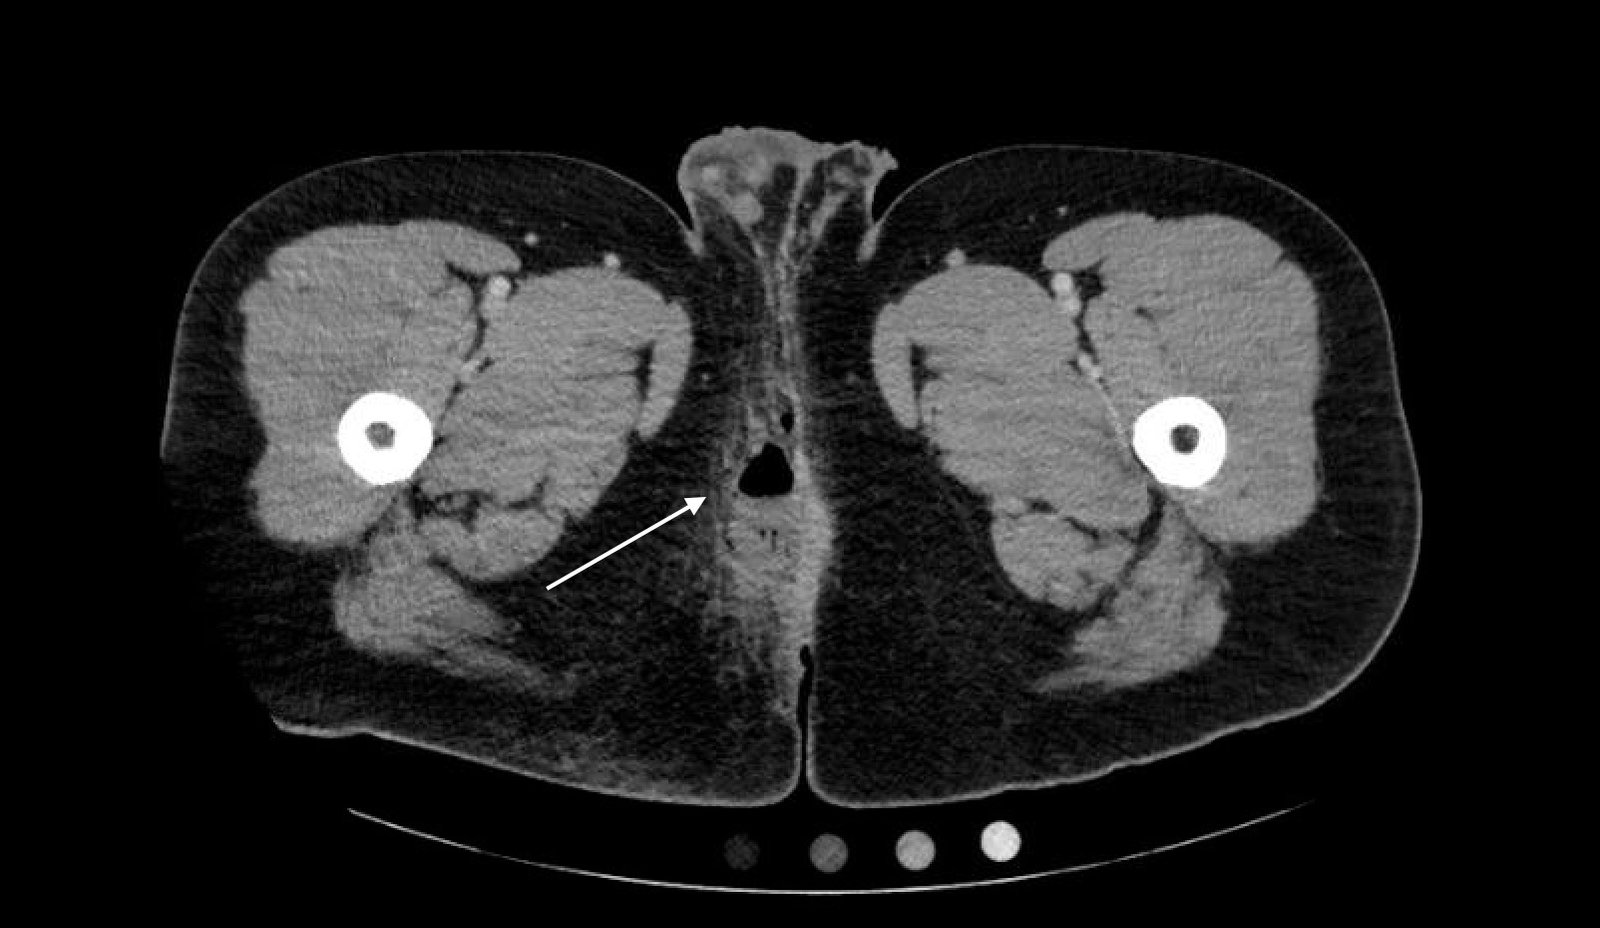

Computed tomography (CT) of the Pelvis with intravenous (IV) contrast revealed a 5.7 cm x 2.4 cm air-fluid collection in the right perianal soft tissue along the right gluteal cleft, with surrounding fat stranding, consistent with a perianal abscess with cellulitis.

A pelvic CT with IV contrast can be used to differentiate between a perianal abscess, which is located beneath the skin of the anal canal and does not transverse the external sphincter, and a perirectal abscess, which is located beyond the external anal sphincter. Ultrasound is emerging as a possible alternative imaging modality; however magnetic resonance imaging (MRI) and CT scans remain the modalities of choice. 3, 4, 5, 6